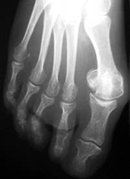

El hallux valgus, popularmente conocido como juanete, es una deformidad del dedo gordo del pie. Esta deformidad altera el funcionamiento normal del pie y puede producir dolor. Se produce con mayor frecuencia en mujeres.

La causa principal es el calzado, motivo por el cual el hallux valgus es más frecuente en mujeres. El primer consejo que damos a nuestros pacientes es calzarse con un zapato cómodo.